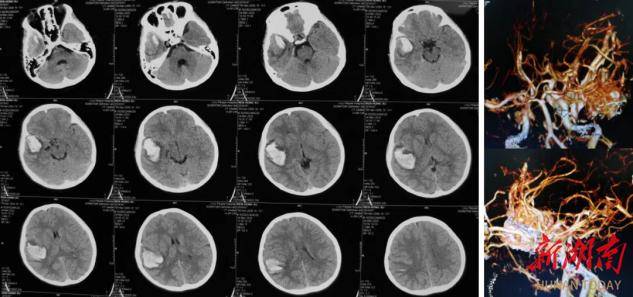

事发当天,张先生正朝着每日100个俯卧撑的目标努力,做到第89个时突然重重砸在瑜伽垫上。他挣扎起身时,突然感到钢针刺进太阳穴般的剧烈头痛,还伴随天旋地转的眩晕感,根本无法站立。家人见状立即拨打120急救电话,将其紧急送医。经头颅CT检查,张先生被确诊为运动相关性脑出血,出血量达15毫升。神经外科・NICU主任钟治军带领团队迅速开展紧急救治,最终助其脱离生命危险。